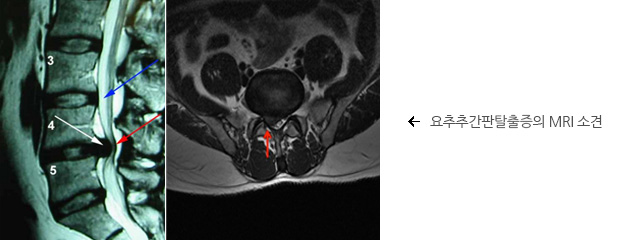

X-ray 상에서도 추간판 탈출증의 간접적인 소견이 관찰될 수는 있으나, 이것만으로 확진할 수는 없습니다. MRI와 CT는 신경이 압박되는 것을 명확하게 보여주는 영상검사입니다. 그 외에 척추관 조영술(myelofram)이나 근전도(EMG)가 필요한 경우도 있습니다.